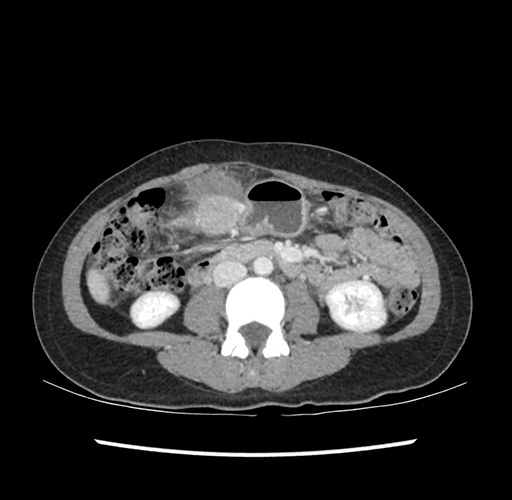

Imaging Analysis

Look through the patient's CT scan to identify any areas of concern for the necessary procedure.

Based on your CT findings, which issue(s) would give reason for "planned slowing down moment(s)" in this case?